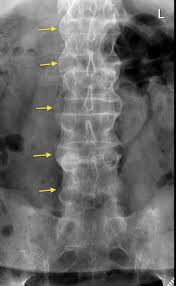

ankylosing spondylitis

systemic illness (predominantly in men 20-40) variant results in pain and stiffness in SI, intervertebral & costovertebral joints, along w/ abnormal union of spinal joints, complete rigidity of spine, usually seen in SI jts (bamboo spine)